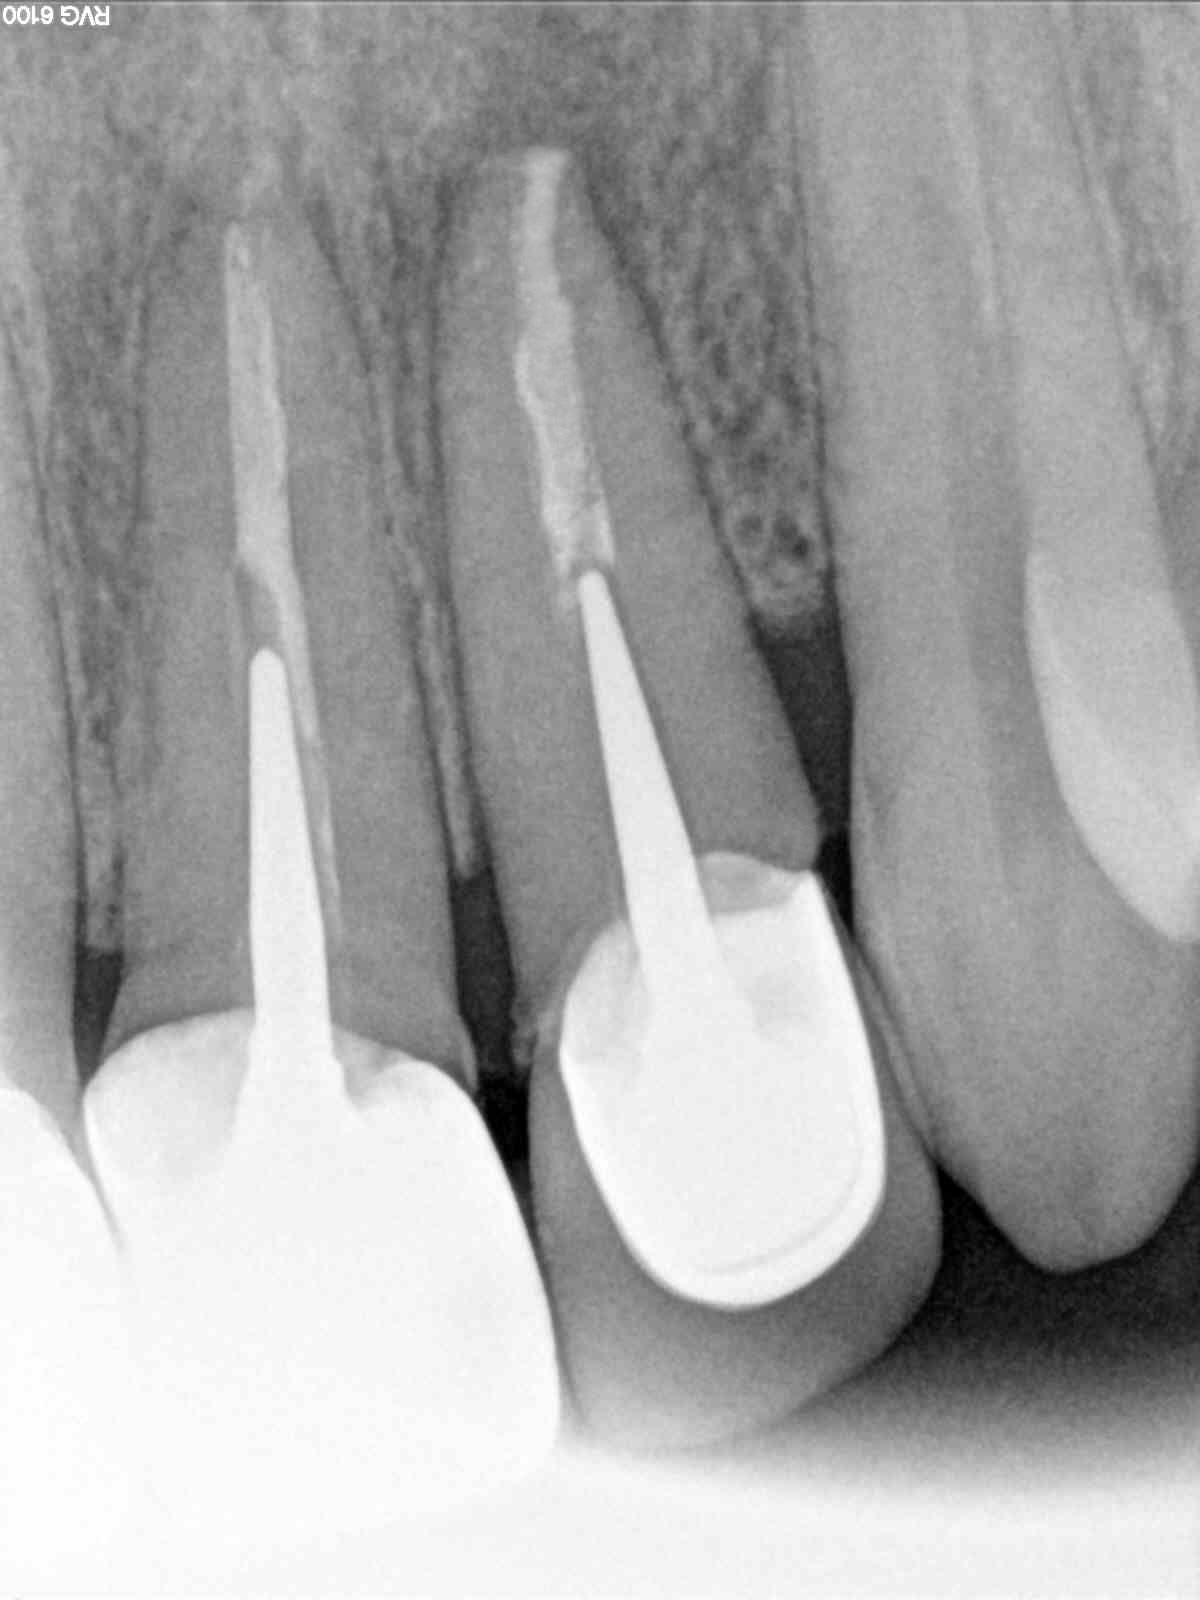

à 4 mois ménage + radio :

- à pu bobo

-à pu fistule

-à pu mobilité

un implant de moins !

l'affaire est dans le sac !

merci enlaye!